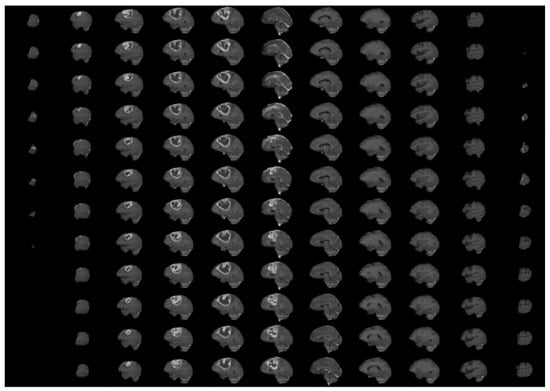

3.1. BraTS 2020 Dataset

3.2. Data Pre-Processing